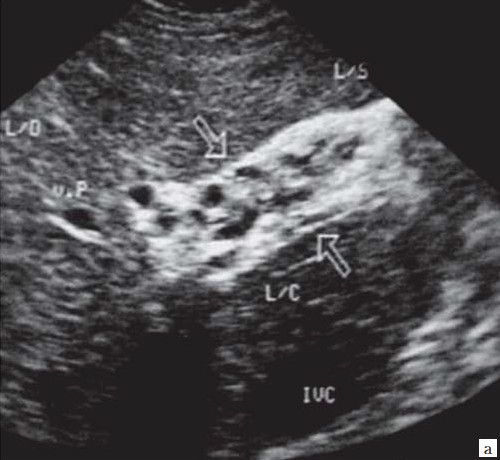

- Ультразвуковое исследование (УЗИ). Основным признаком МЖ при УЗИ является расширение внутрипеченочных желчных протоков (рис. 1). УЗИ позволяет не только выявить билиарную гипертензию, но и установить уровень блока. При высоком билиарном блоке (обтурация на уровне ворот печени) при УЗИ визуализируются расширенные внутрипеченочные протоки при нормальном диаметре ОЖП (до 6 мм), желчный пузырь чаще нормальных размеров или уменьшен, возможно выявление в воротах печени объемного образования.При низком билиарном блоке (обтурация на уровне холедоха, головки ПЖ, БДС) кроме расширенных внутрипеченочных протоков визуализируются расширенные внепеченочные протоки, желчный пузырь увеличен (рис. 2). Если низкий блок обусловлен индуративным панкреатитом, при УЗИ имеет место увеличение органа в размере, могут выявляться кальцинаты в ПЖ (рис. 3). При опухоли головки ПЖ на фоне билиарной гипертензии визуализируется объемное образование в ПЖ (рис. 4). Критериями гипертензии главного панкреатического протока служит его расширение более 2 мм в теле и более 3 мм в головке ПЖ.При ЖКБ, осложненной холедохолитиазом, выявляется увеличенный желчный пузырь с конкрементами, а также конкременты в холедохе (рис. 5).Диагностируют очаговые поражения печени: эхинококковые и альвеококковые кисты; увеличенные лимфоузлы; местатазы.

Рис. 2. Эхографическая картина низкого печеночного блока, обусловленного опухолью головки ПЖ.

а) Расширенные внутрипеченочные протоки.